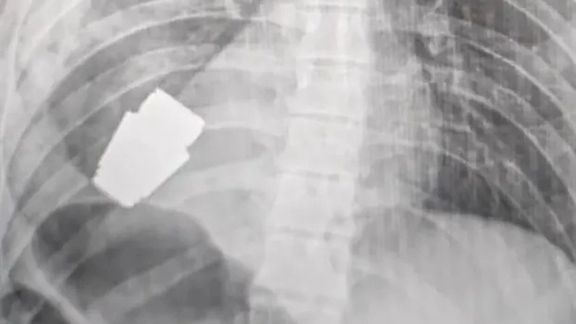

جراحان یک نارنجک منفجر ناشده را از قفسه سینه یک سرباز اوکراینی بیرون کشیدند

هانا مالیار، معاون وزیر دفاع اوکراین تصویری را از رادیوگرافی قفسه سینه یک سرباز اوکراینی منتشر کرد که جراحان یک نارنجنک منفجر ناشده را از آن بیرون کشیدهاند. در همین حال مشاور وزیر داخله اوکراین، روش این عمل را به گونهای توصیف کرد که در «کتابهای درسی پزشکی ثبت خواهد شد.»